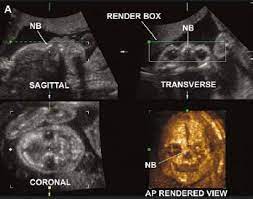

If the 2D ultrasound does not demonstrate two nasal bones then 3D ultasound may be useful. An ultrasound scan There is no risk to the baby from either of these procedures. October 15 2018 Shane Dale According to the National Down Syndrome Society NDSS during the normal fertilization of a womans egg by a mans sperm the resulting nucleus of each cell in a fetus contains 23 pairs of chromosomes half of which are inherited from each parent.

For this reason 3D ultrasound reconstruction of the nasal bone and other facial bones is useful. At this stage the babys legs arms fingers and toes should be fully formed. Mothers should not be encouraged to have an ultrasound called a.